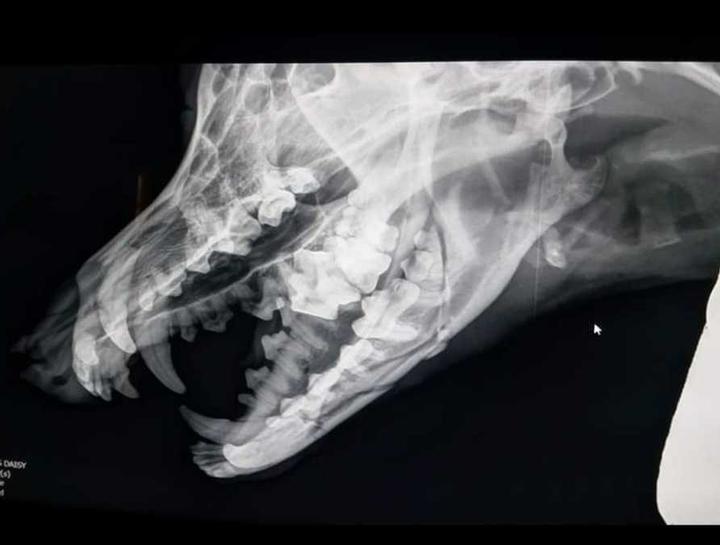

Xrays for Cats & Dogs

Pet Digital Radiology

Digital x-rays assist in diagnosing illness & injury.